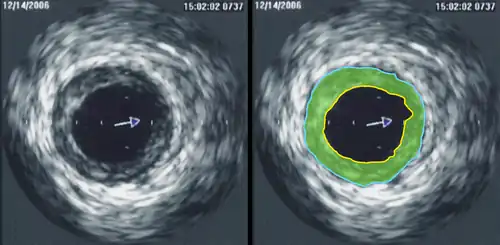

Intravascular ultrasound image of a coronary artery (left), with color-coding on the right, delineating the lumen (yellow), external elastic membrane (blue) and the atherosclerotic plaque burden (green)

In angiology or vascular medicine, duplex ultrasound (B Mode imaging combined with Doppler flow measurement) is used to diagnose arterial and venous disease. This is particularly important in potential neurologic problems, where carotid ultrasound is commonly used for assessing blood flow and potential or suspected stenosis in the carotid arteries, while transcranial Doppler is used for imaging flow in the intracerebral arteries.

Intravascular ultrasound (IVUS) uses a specially designed catheter with a miniaturized ultrasound probe attached to its distal end, which is then threaded inside a blood vessel. The proximal end of the catheter is attached to computerized ultrasound equipment and allows the application of ultrasound technology, such as a piezoelectric transducer or capacitive micromachined ultrasonic transducer, to visualize the endothelium of blood vessels in living individuals.[12]